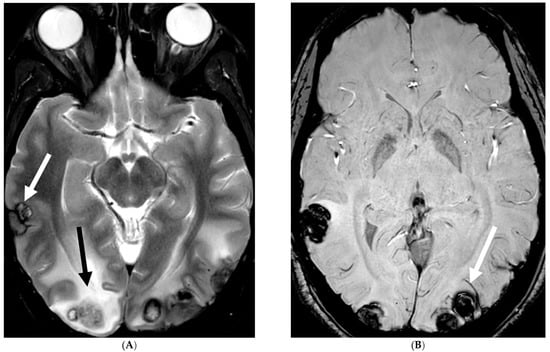

E. coli is another common neonatal and infantile cause of bacterial meningitis. There is characteristic diffusion restriction in the extra-axial collections along with ventriculomegaly and/or ventriculitis [74]. To note, extra-axial empyema is also common with S. pneumoniae, but occur in an older age group. Serratia marcescens and Citrobacter are two uncommon pathogens causing meningitis in neonates with fulminant disease course. They lead to large parenchymal abscesses with striated appearance on T2W images and foci of susceptibility. N. meningitidies causes typical gyriform cortical enhancement consistent with cerebritis predominantly involving the occipital lobes (Figure 12) [74].

Figure 12.

Axial DWI (A), axial SWI (B), sagittal T2 (C), axial ASL (D) and coronal T1 post contrast (E): 11-day-old female presented with seizures and lethargic. Restricted diffusion is noted in the sulci along the bilateral frontal convexities, concerning for meningitis (arrows). Curvilinear susceptibility in the extra-axial spaces of bilateral frontal convexities, consistent with thrombosed cortical veins (curved arrows). Cortical T2 hyperintensity is seen in the bilateral frontal and parietal lobes with corresponding hyperperfusion in keeping with extensive cerebritis (dashed arrows). Diffuse leptomeningeal and pachymeningeal enhancement is seen (open arrows). Overall features represent meningitis and cerebritis. Cerebrospinal fluid analysis: Group B streptococcus.